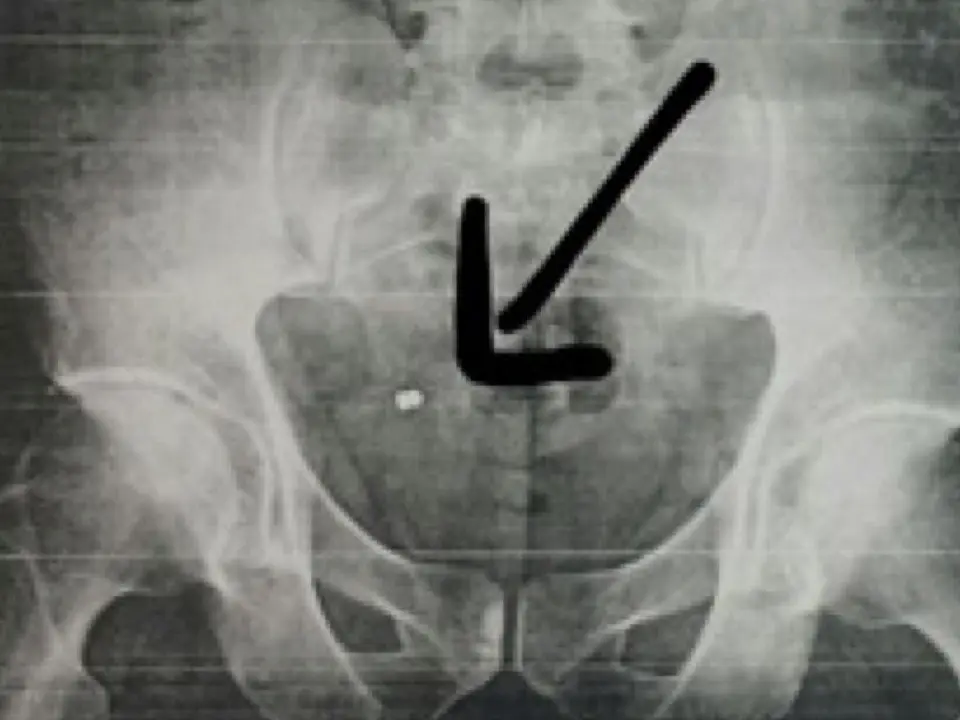

Fue en su casa cuando se dio cuenta de que tenía un orificio, volviendo al día siguiente a la mutua donde ya sí le hicieron una radiografía y comprobaron que tenía un perdigón incrustado en su nalga derecha, como se puede ver en la imagen que publicamos a continuación, cedida por El Heraldo del Henares.

El empleado municipal fue derivado al Hospital de Fremap en Majadahonda donde, una semana después, será operado este jueves para poder extraerle el perdigón.